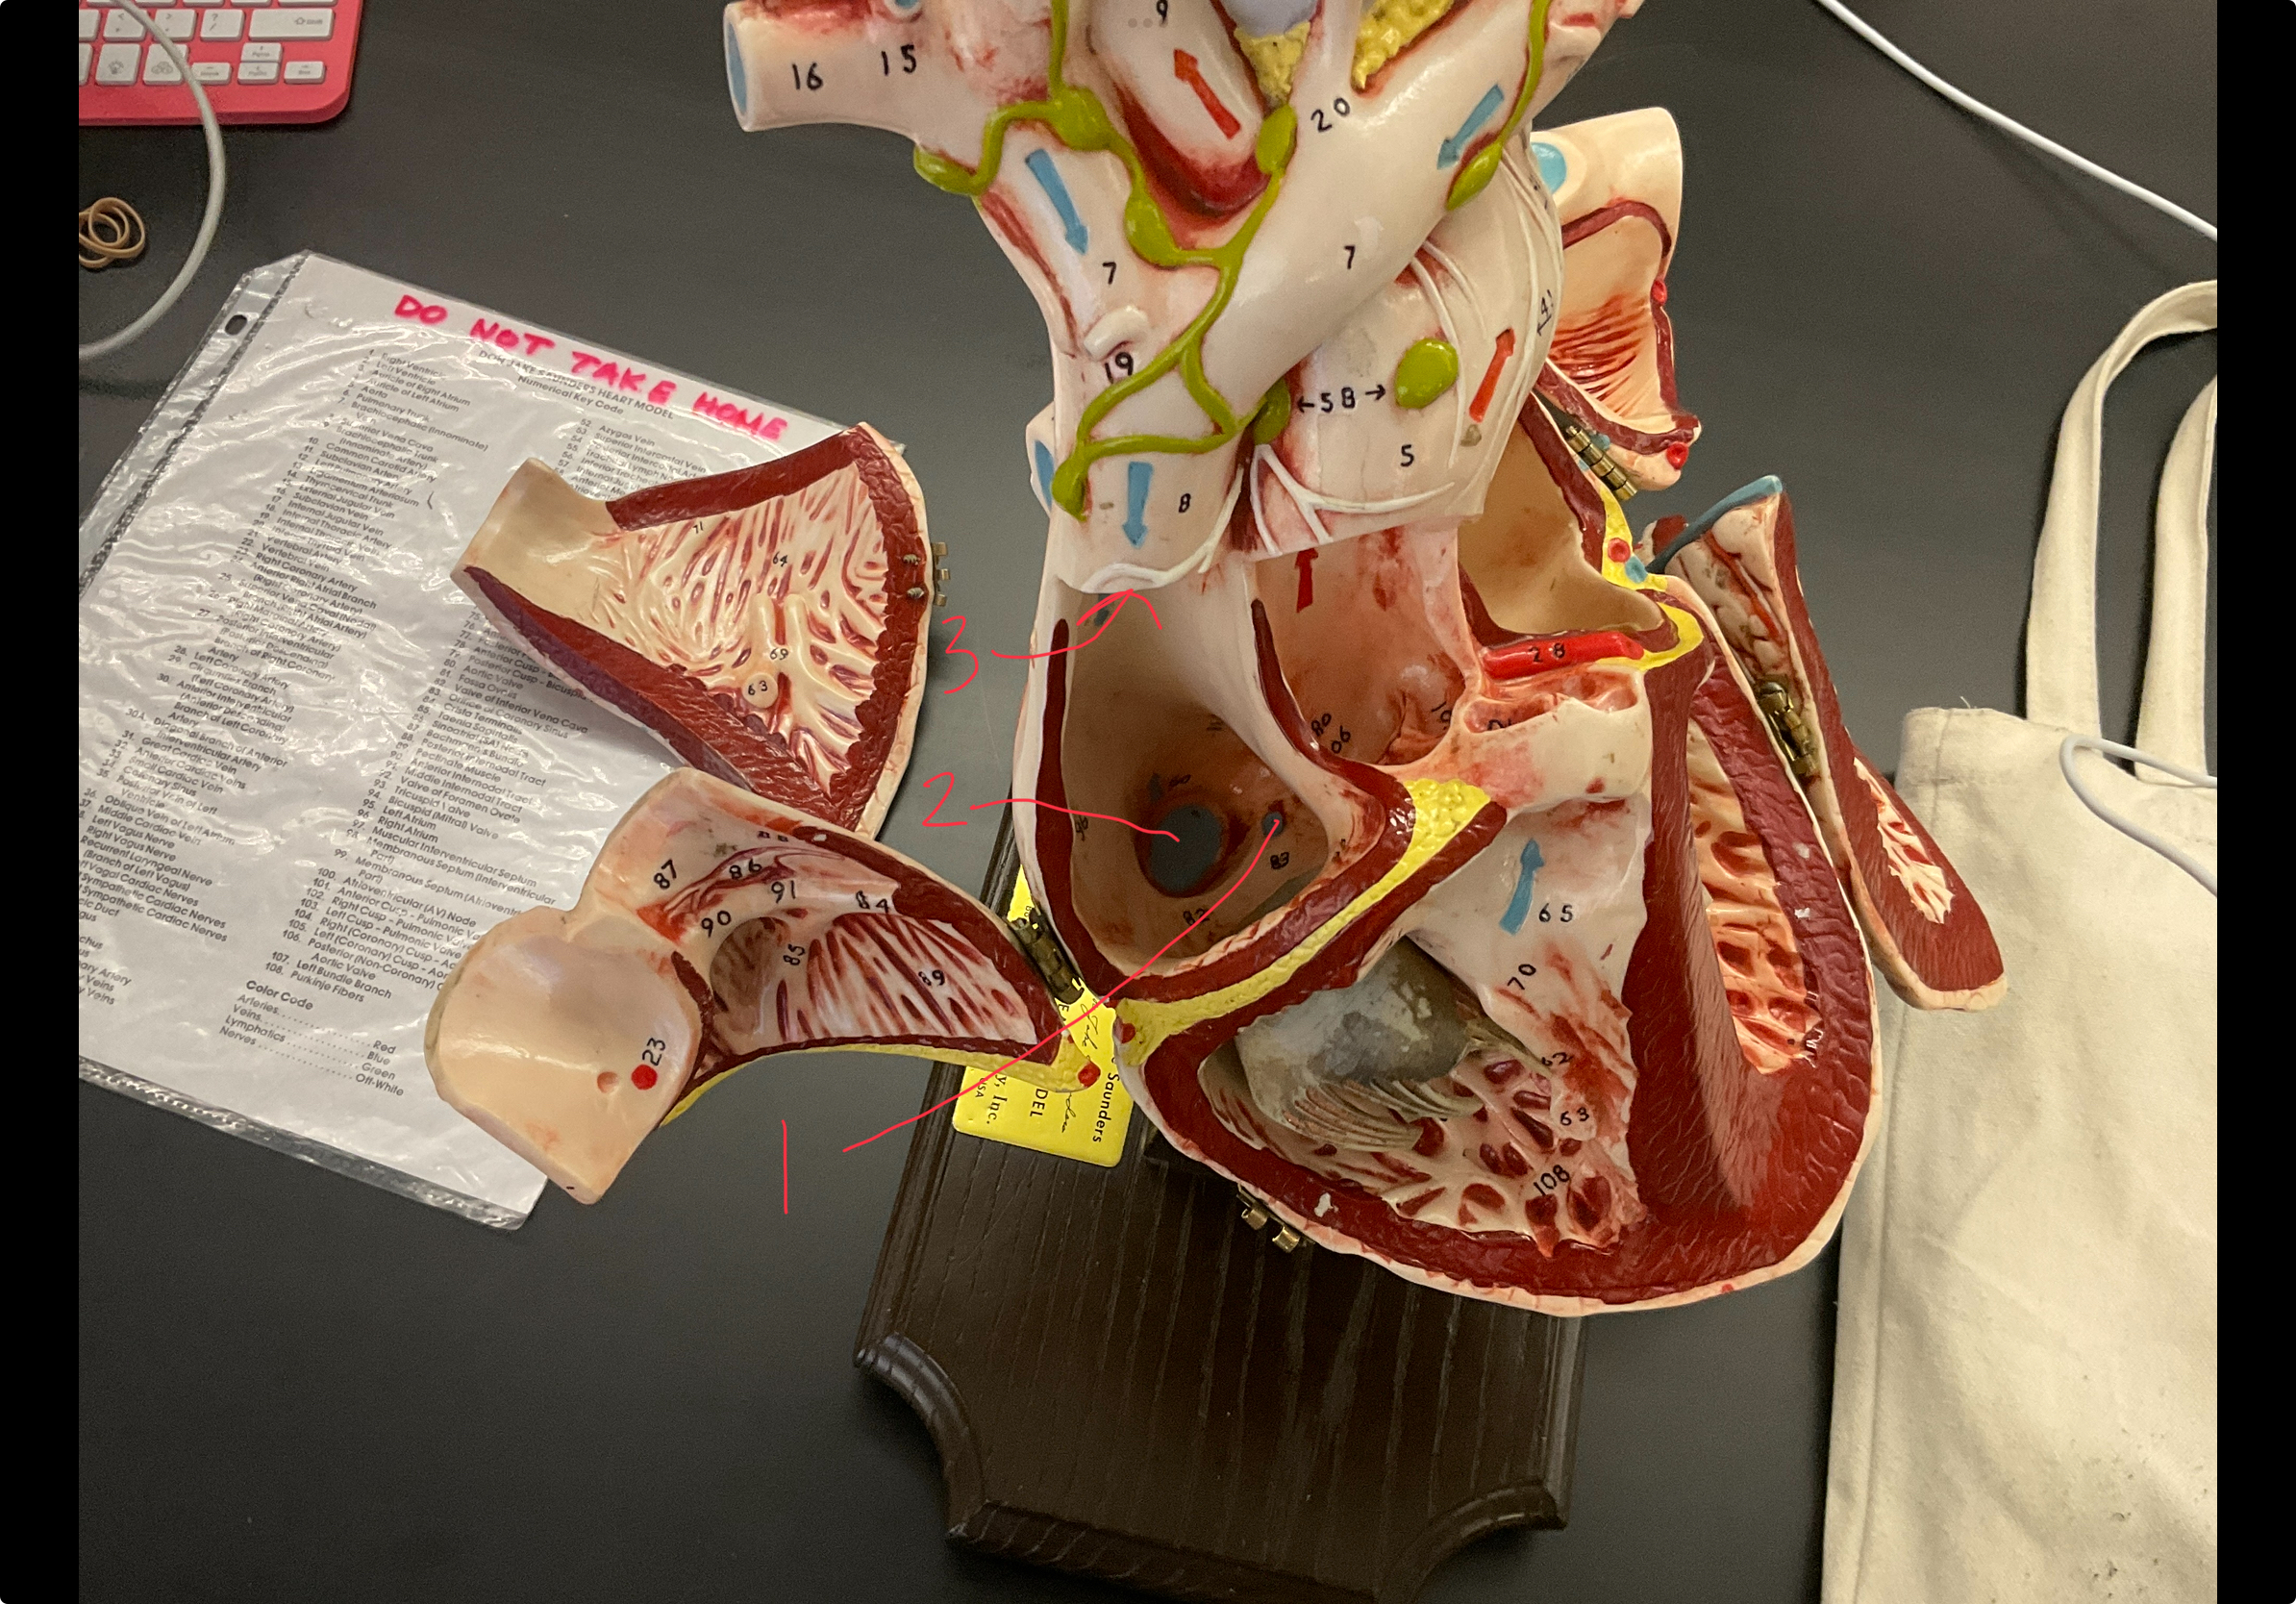

1

epicardium

2

3

endocardium

3

2

myocardium

4

1

coronary sinus

5

2

inferior vena cava

6

3

superior vena cava

7

1

right ventricle

8

2

left ventricle

9

3

bicuspid

10

4

tricuspid

11

5

interventricullar septum

12

6

left atrium

13

7

aorta

14

8

aortic trunk

15

9

pulmonary semi-lunar valve

16

10

atrevoventricullar sulus

17

11 (not smooth part)

trubeculae carneae

18

1

papillary muscle

19

2

chordae tendineae

20

4

pulmonary trunk

21

6

aortic trunk

22

aortic semi lunar valve

New cards

anterior inter ventricular sulcus